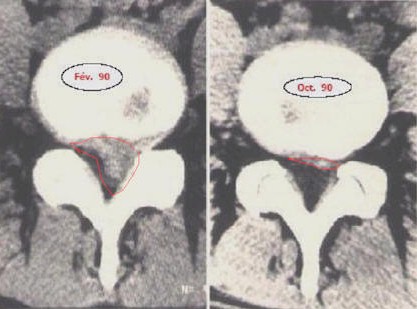

hd

Figure 1 : Imagerie médicale montrant la régression de plus de 90% d’une hernie discale lombaire (entourée en rouge) sur une période de 8 mois.